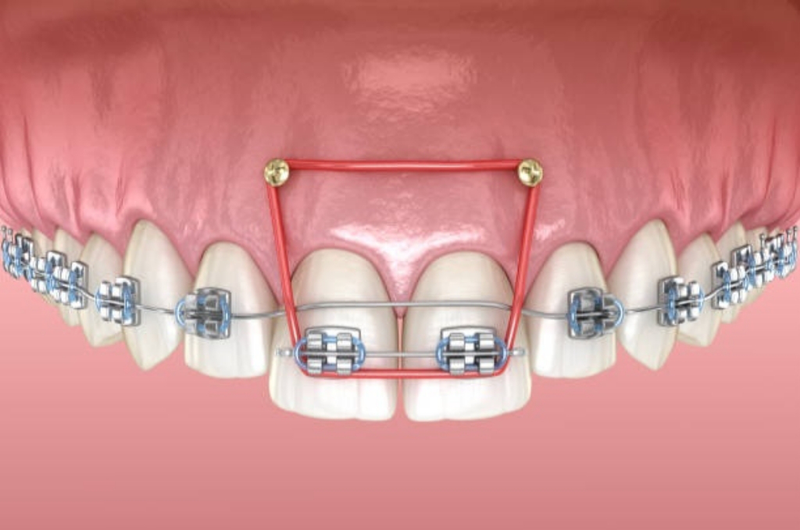

Vít niềng răng (hay còn gọi là minivis chỉnh nha) là một loại vít nhỏ bằng titanium được cắm trực tiếp vào xương hàm nhằm tạo điểm neo cố định trong quá trình chỉnh nha. Không phải ai niềng răng cũng cần cắm vít, phương pháp này thường được chỉ định trong những trường hợp chỉnh nha phức tạp, khi mà phương pháp niềng răng thông thường không đủ lực hoặc không kiểm soát tốt hướng dịch chuyển của răng.

Việc cắm vít khi niềng răng giúp bác sĩ kiểm soát lực kéo tốt hơn, hạn chế tình trạng răng bị xô lệch không đúng hướng. Nhờ có vít chỉnh nha, các ca hô, móm, răng chìa nhiều hoặc cần kéo lùi răng hàm sẽ đạt kết quả cao hơn. Đồng thời với sự hỗ trợ của vít niềng răng sẽ giúp rút ngắn thời gian niềng hơn so với phương pháp thông thường.

Trên thực tế, vít niềng răng bị lung lay không phải lúc nào cũng nguy hiểm, tuy nhiên cũng cần được bác sĩ kiểm tra và xử lý kịp thời. Vít chỉnh nha chỉ đóng vai trò là điểm neo tạm thời của răng trong quá trình niềng răng, không tích hợp vĩnh viễn vào xương hàm như Implant. Do đó mà vít cắm có thể bị lung lay sau một thời sinh hoạt. Nếu vít chỉ lung lay nhẹ, không gây đau nhức, sưng viêm hay ảnh hưởng đến lực kéo chỉnh nha thì bác sĩ có thể điều chỉnh lực và tiếp tục theo dõi.

Ngược lại, nếu vít lung lay nhiều, gây đau, viêm nướu hoặc làm gián đoạn quá trình kéo răng, bác sĩ sẽ chỉ định tháo vít và cắm lại vít mới ở vị trí phù hợp hơn. Việc xử lý đúng thời điểm và đúng kỹ thuật không làm ảnh hưởng đến kết quả niềng răng. Tuy nhiên, bạn cũng không nên tự ý chạm, xoay hoặc để vít lung lay thời gian dài vì nó có thể gây viêm nhiễm và làm chậm tiến độ chỉnh nha.